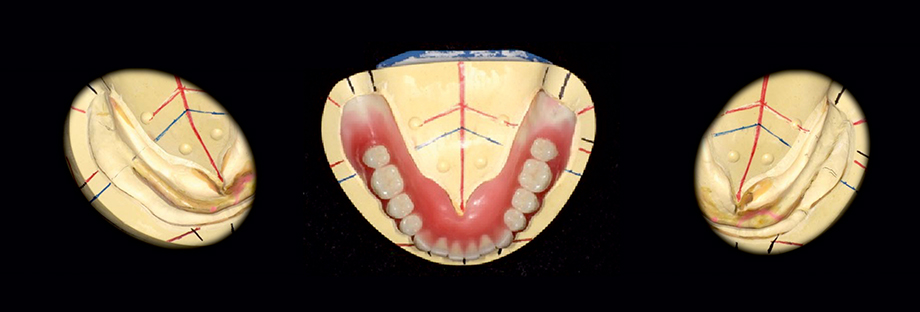

Aufstellung der Zähne unter Berücksichtigung der hydrostatischen Stabilität bei größtmöglicher Ästhetik im Frontzahnbereich und Stabilität im Seitenzahnbereich. Speziell bei der Unterkieferprothese.

Das Easy Set Up Konzept ermöglicht ein einfaches Aufstellen.

Um die Saugeffizienz der Unterkieferprothesen zu optimieren, ist es essentiell, dass die Prothesenränder so gut wie möglich abschließen. Dies gewährleistet eine okklusale Stabilität der Prothese. Hierzu ist eine funktionale Form der konfektionierten Prothesenzähne wichtig.